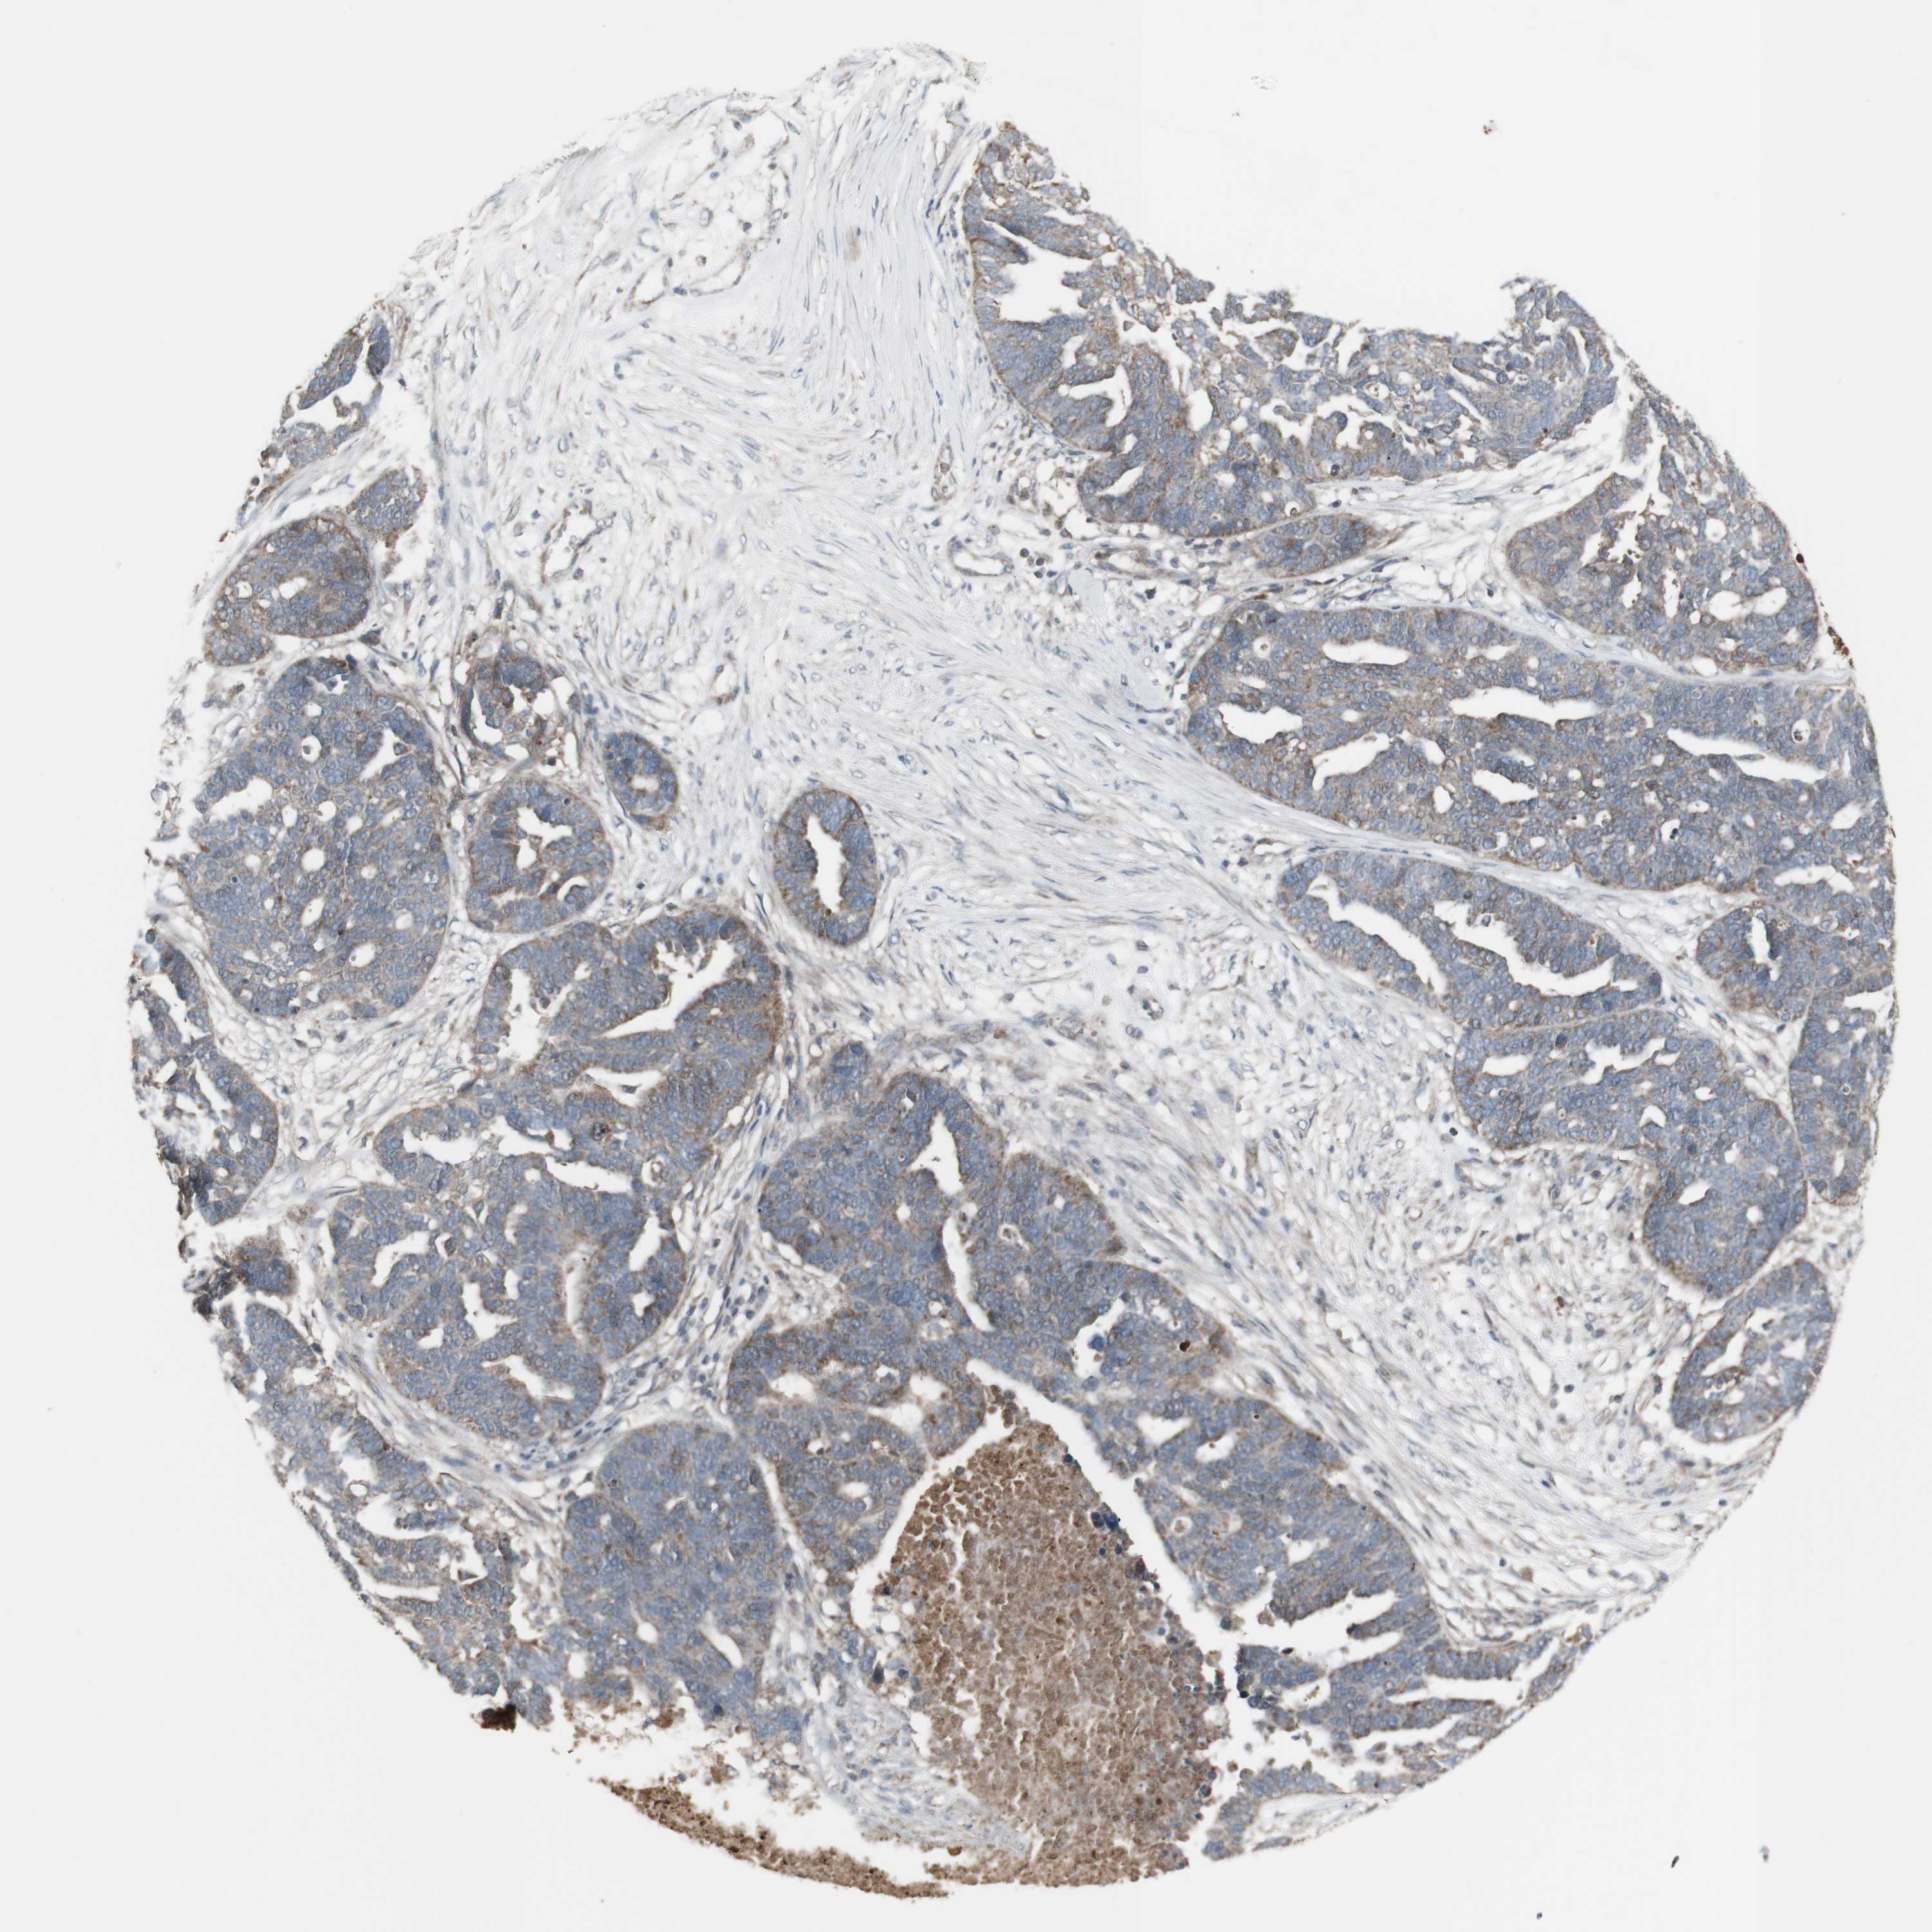

OVARIAN CANCER - Protein expressioni

A mouse-over function shows sample information and annotation data. Click on an image to view it in a full screen mode. Samples can be filtered based on level of antibody staining by selecting one or several of the following categories: high, medium, low and not detected. The assay and annotation is described here.

Note that samples used for immunohistochemistry by the Human Protein Atlas do not correspond to samples in the TCGA dataset.

Antibody stainingi

Antibody staining in the annotated cell types in the current human tissue is reported as not detected, low, medium, or high, based on conventional immunohistochemistry profiling in selected tissues. This score is based on the combination of the staining intensity and fraction of stained cells.

Each image is clickable and will lead to virtual microscopy that enables deeper exploration of all samples and also displays staining intensity scores, fraction scores and subcellular localization as well as patient and tissue information for each sample.

Antibody CAB016305

Cystadenocarcinoma, serous, NOS